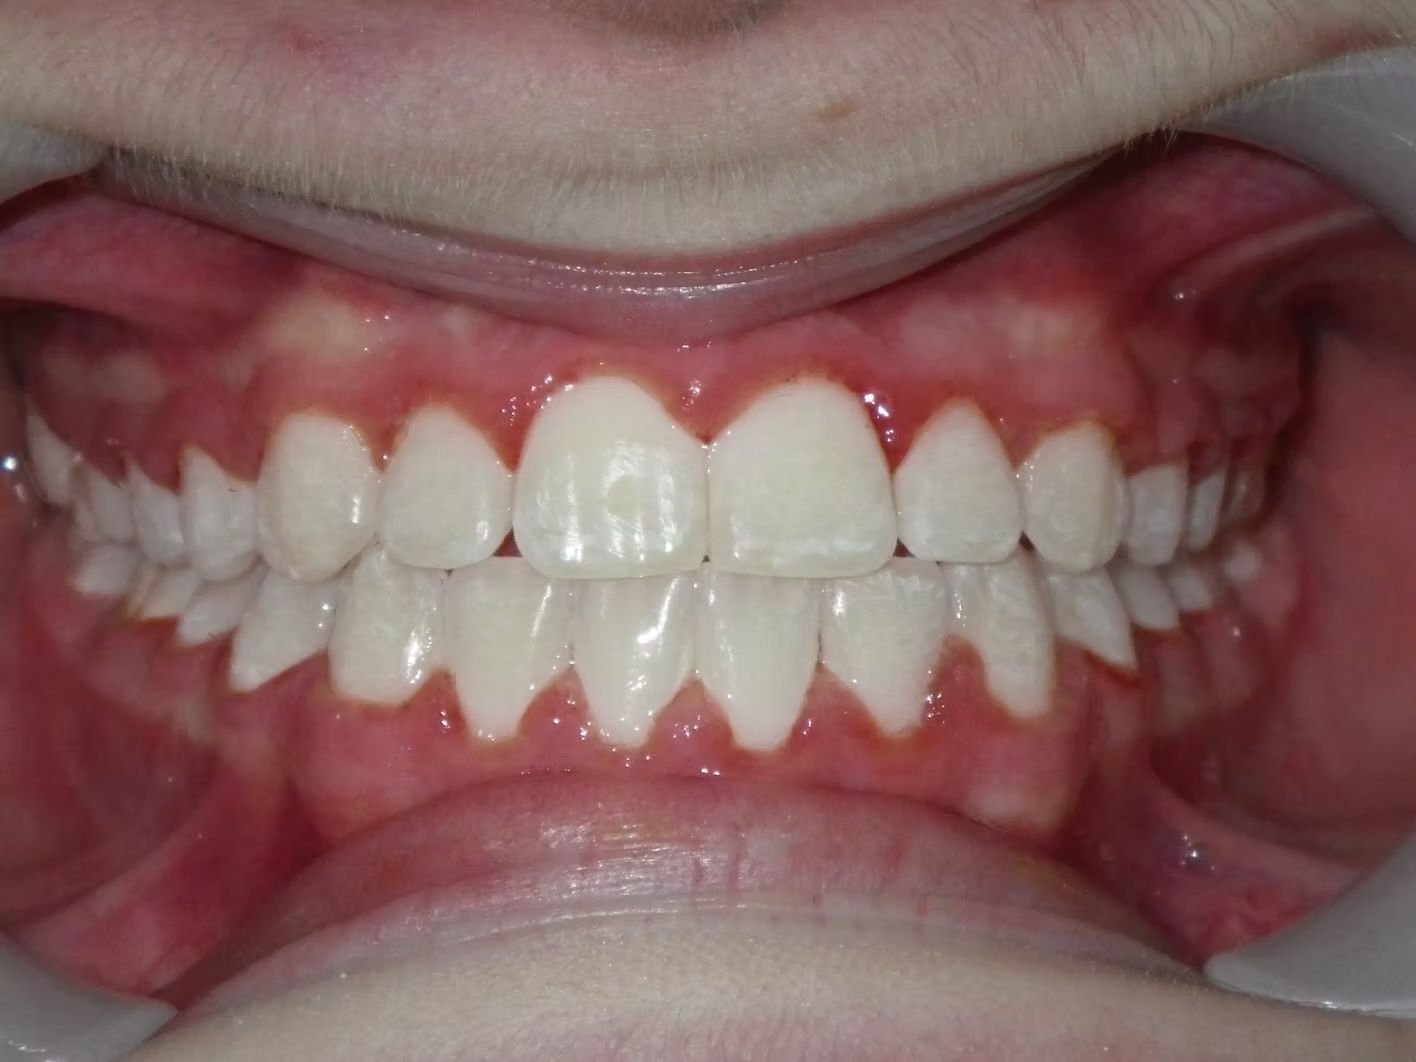

AMBER

Amber, began treatment with Dr. Bret because she didn't like that her front teeth overlapped each other. She had narrow top and bottom dental arches with severe crowding of her upper and lower teeth. She was treated with braces on the upper and lower teeth, and we used the braces to widen the smile. What a change!